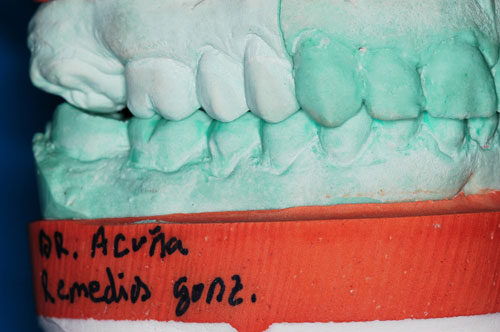

ESTUDIO ESTÁTICO DE LOS MODELOS PREVIOS A LA PRIMERA REHABILITACIÓN APORTADOS POR LA ENFERMA:Modelos Color Blanco

B- ESTUDIO ESTÁTICO DE LOS MODELOS PREVIOS A LA 1ª REHABILITACIÓN APORTADOS POR LA ENFERMA: (La situación oclusal que la enferma tenía antes de que la tocara un dentista (MODELOS COLOR BLANCO)

Diferencias entre ambos modelos:

A nivel de segundos molares= 4 mm +

A nivel de primeros molares= 3,50 mm +

A nivel de incisivo central=5,50 mm +

Luego de observar detenidamente el aumento de altura entre los primeros y los segundos modelos, observamos un detalle que de haberlo visto en primer término, nos habría facilitado enormemente el diagnóstico :

Antes de la 1ª intervención, los segundos molares superior e inferior derechos tocaban.